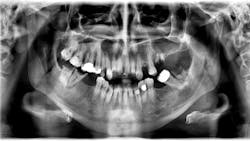

Patient: 37-year-old male

- Badly decayed teeth on the lower right side

- Apical radiolucency and associated swelling in the buccal vestibule

- Well-defined radiolucency above the apexes of teeth nos. 5-9

- Some expansion around the bone

- Lesion not fluctuant or mobile